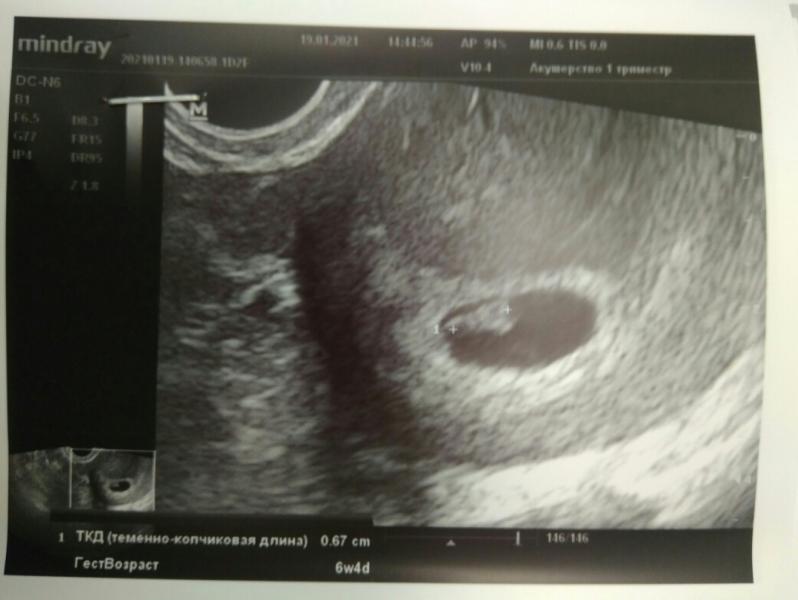

Повторюсь, 5 января я узнала о беременности и начала метаться в дальнейших действиях. Сначала записалась в Гемотест на ХГЧ, потом подумала и решила лучше сразу на узи пойти (хгч в итоге не сдавала вообще). У меня был нерв на тему маточная/нематочная, хотелось узнать этот момент. Я выждала 4 дня и на сроке ровно 5 недель попала на узи. Меня успокоили, что беременность маточная, малышок уже 1,8 мм😍 (фото 1). Мы с мужем подумали и решили за...